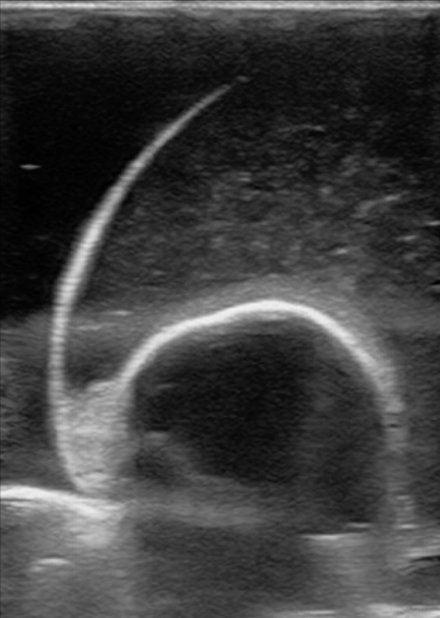

Figure 13. A model with normal testicle, large epididymis, and an epididymal cyst.